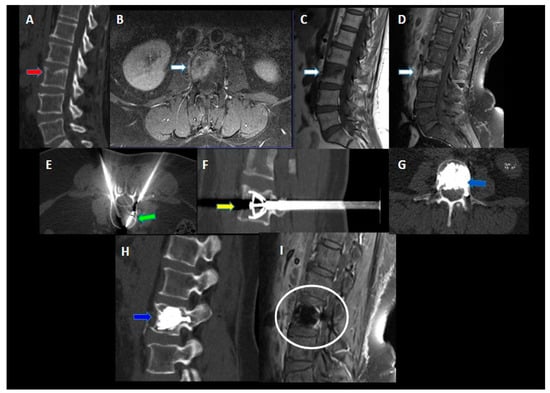

Contrast-enhanced CT scans performed at 1, 3, and 6 months and contrast-enhanced spine MRI performed at 6 months after the procedure showed no local recurrence, implant displacement, or new fractures in the treated site (Figure 6).

Figure 6. A 50-year-old female with a history of breast cancer with lumbar pain. (A) A CT of the lumbar spine in the sagittal plane shows a compression fracture of the superior endplate of the vertebral body of L3 (red arrow). (BD) CE-MRI (in (B) the axial plane—CE T1 Fat-Sat sequence, in (C) the sagittal plane—T1 TSE sequence, and in (D) the sagittal plane—sagittal plane—CE T1 Fat-Sat sequence) confirms the presence of active vertebral fracture associated with a hyperintense focal lesion in T1 Fat-Sat sequences (white arrows). (E) Axial CT image; right microwave antenna inserted coaxially through the cannula for ablation (green arrow). (F) Sagittal MIP (maximum intensity projection) image after the opening of the SJ implants (yellow arrow). (G,H) Post-procedure control—CT in the axial (G) and sagittal (H) planes showed a correct expansion of the vertebra and a homogeneous cement filling (blue arrows). No procedural complications were observed. (I) follow-up MRI 12 months after the procedure (the sagittal plane-T1 Fat-Sat sequence): no evidence of local recurrence of the disease or complications in the treated vertebra (white circle).